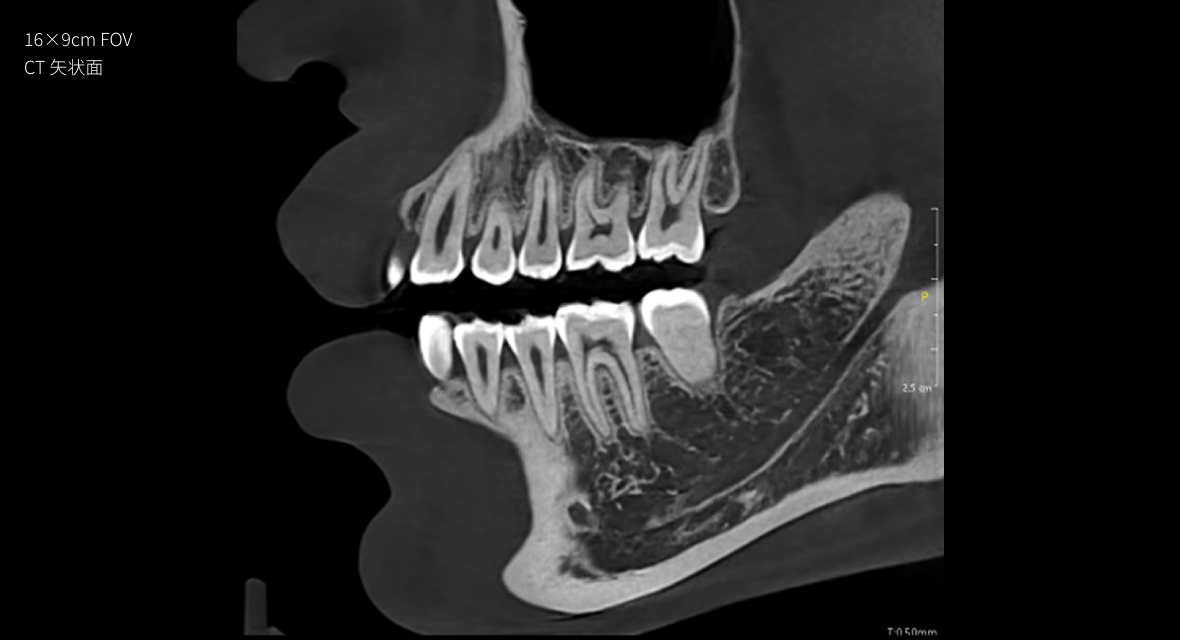

20×18cm

非拼接大视野

28lp/cm

高精准

Physics-driven系列伪影校正算法

实现高清精准成像

物理驱动

伪影校正算法